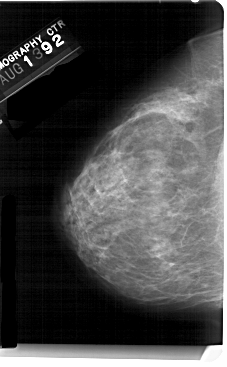

A_1434_1.LEFT_CC

LEFT_CC LINES 5491 PIXELS_PER_LINE 3391 BITS_PER_PIXEL 12 RESOLUTION 43.5 NON_OVERLAY